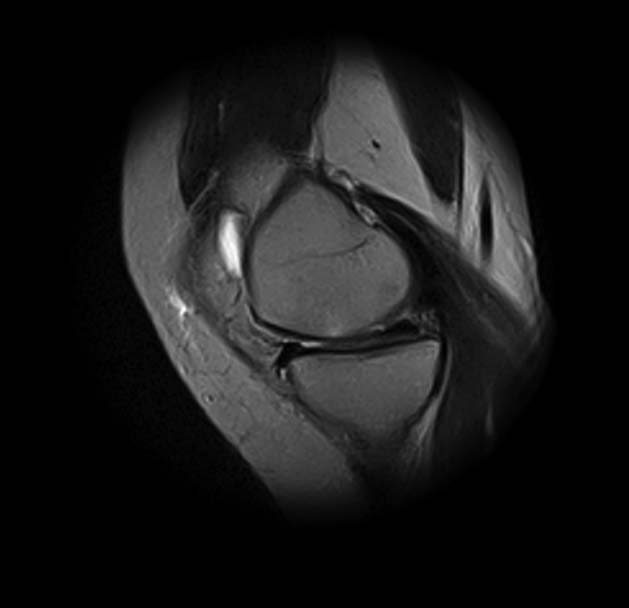

Женщина 45 лет, в течение 5 лет отмечает боли в передне-наружном отделе левого коленного сустава, при повороте туловища и фиксированной стопе, а также при спуске по лестнице боли усиливаются. Клинически - болезненность в проекции переднего рога и тела латерального мениска. Но меня смущает МРТ - нет ли кистозного перерождения и кисты мениска?

добрый день! Не очень понятен принцип, по которому отбирались снимки МРТ. Большинство из них не показательны. Вижу пока только повреждение хряща на феморопателлярной поверхности. Хлтелось бы посмотреть диск целиком

На снимках повреждений наружного мениска не вижу и кисты мениска не вижу. Есть повреждение хряща на передней поверхности внутреннего мыщелка бедра. Вполне может оказаться, что повреждение лоскутное. А какая консервативная терапия проводилась?